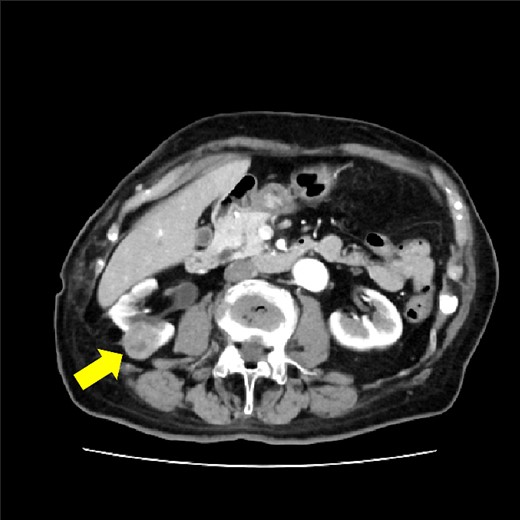

The patient was an 85-year-old woman with two pregnancies and two births. Her body mass index was 25 kg/m2. She had a history of hypertension, rheumatism, and open right pyeloplasty performed for stenosis of the right renal pelvic ureteric junction. A tumor in the right kidney was detected on an abdominal ultrasound examination and computed tomography (CT); the tumor size was about 30 mm (Fig. 1). A transperitoneal laparoscopic nephrectomy was performed. The operation time was 1 h and 52 min, and the blood loss was 10 ml. The surgery was completed without complications.

CT showing 30 mm right renal cell carcinoma. The arrow shows the tumor.